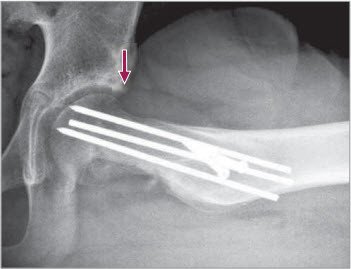

Postoperatives Bild

3 Postoperatives Bild in der AP-Projektion nach offener Epiphysenreposition nach Trochanter flip-Ostoetomie

nach offener Reposition

4 Postoperatives seitliches Bild nach offener Reposition. Der Pfeil zeigt (vorne) die reponierte Kalotte unter leichter Verkürzung des Schenkelhalses, vergleiche präoperatives Bild Abb 2